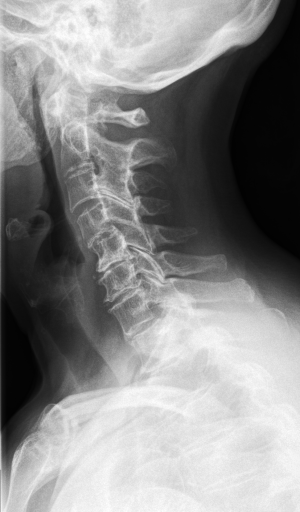

Details of the IRMA database is described in literature [24],[27],[25]. IRMA dataset offers 12,677 images for training and 1,733 images for testing. Figure 4 shows some sample images from the dataset long with their IRMA code in the format TTTT-DDD-AAA-BBB.